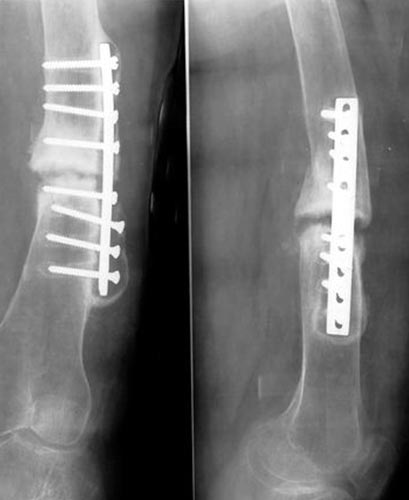

病例二、患者62岁,股骨中1/3骨折骨不连2年,3次钢板手术失败,明显畸形。

同上述方法治疗,9个月后骨折愈合。